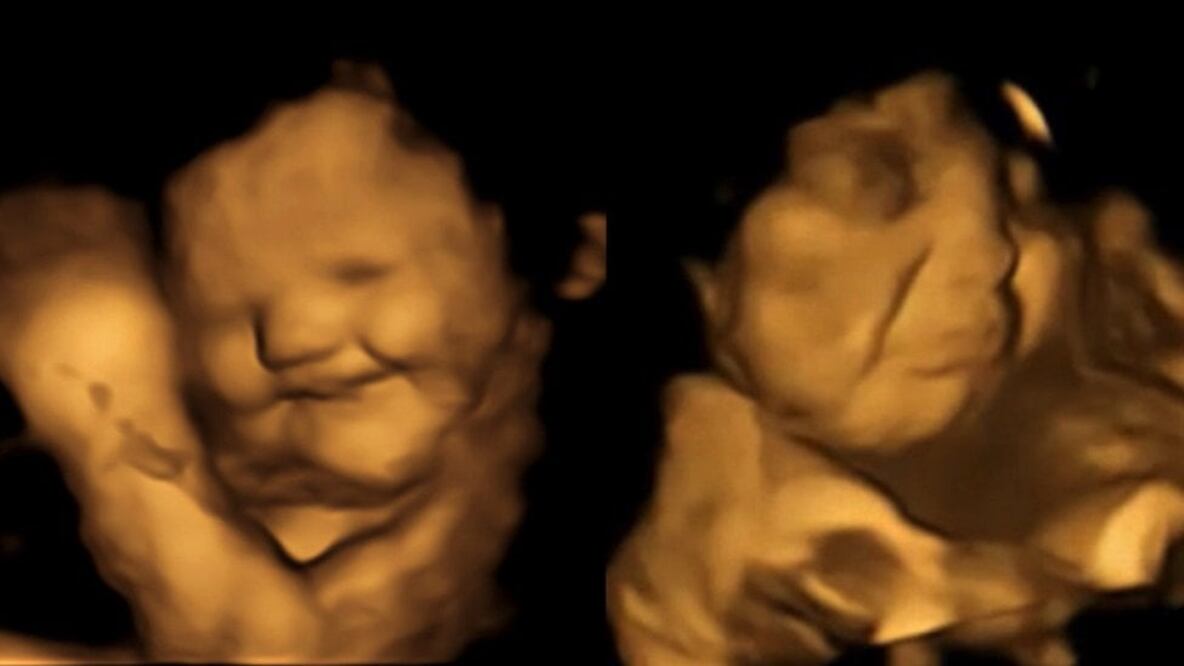

Si el sabor de la col rizada te hace fruncir el ceño, no estás sola. Los científicos han descubierto que los fetos en el útero parecen sonreír después de que sus madres comen zanahorias y fruncen el ceño después de que coman esa col.

En el estudio que publicaron en la revista "Psychological Science", el grupo informó que 20 minutos después de que las madres tragaran las cápsulas las ecografías 4D mostraron que la mayoría de los fetos expuestos a la col parecían hacer una mueca.

Mientras tanto, los expuestos a las zanahorias parecían estar sonriendo.

El grupo de control de las 30 mujeres embarazadas que no comieron nada no tuvo las mismas respuestas.

Sin embargo, agrega que si bien las imágenes de ultrasonido sugieren una reacción similar a la de un adulto que prueba algo amargo, aún no se sabe si los bebés por nacer realmente experimentan emociones o disgustos.

Las muecas y sonrisas que se ven en los ultrasonidos "podrían ser solo movimientos musculares que reaccionan a un sabor amargo", dice Reissland, aunque agrega que es sabido que los fetos hacen expresiones faciales.